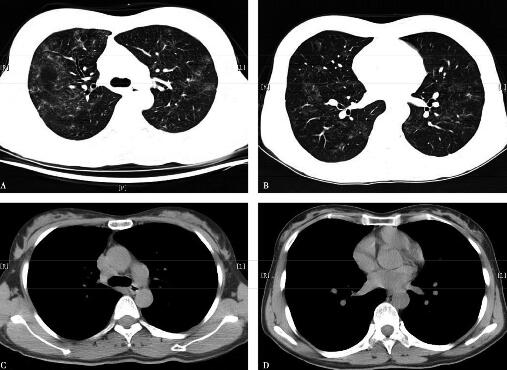

七、治疗方案及疗效

2009年3月给予泼尼松40mg/d[0.75mg/(kg·d)],病情好转,2009年6月9日复查胸部CT,提示双肺病变吸收明显,遗留条索影,纵隔淋巴结缩小(图4)。逐渐规律减量至停用,总疗程1.5年,外院复查胸部CT提示肺部病变吸收,纵隔淋巴结消失。

图4